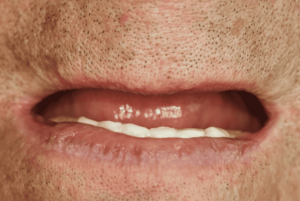

Caso de éxito 1